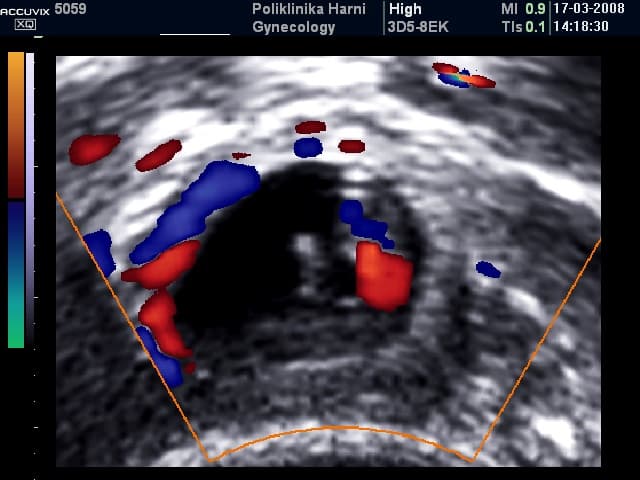

Kod vaginalnog pregleda u početnim stadijima ne mora se nalaziti nikakvih abnormalnosti, dok se kod uznapredovalih stadija ili krvarenja u trbuh palpira se adneksalna masa uz izrazitu bolnost pri pomicanju vrata maternice. Sigurni ultrazvučni znak ektopične trudnoće je nalaz vitalnog embrija izvan maternice. Vjerojatni znaci / trijas ultrazvučnih biljega za ektopiočnu trudnoću su nedostatak ultrazvučnih znakova trudnoće u maternici, adneksalni tumor i prisutnost tekućine u trbuhu. Sumnjivi ultrazvučni nalaz je već i nedostatak nalaza embrija u maternici kod izostanka menstruacije.